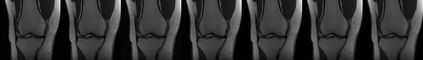

Magnetic Resonance Imaging (MRI) has excellent soft tissue contrast but is hindered by an inherently slow data acquisition process. Compressed sensing, which reconstructs sparse signals from incoherently sampled data, has been widely applied to accelerate MRI acquisitions. Compressed sensing MRI requires one or more model parameters to be tuned, which is usually done by hand, giving sub-optimal tuning in general. To address this issue, we build on previous work by the authors on the single-coil Variable Density Approximate Message Passing (VDAMP) algorithm, extending the framework to multiple receiver coils to propose the Parallel VDAMP (P-VDAMP) algorithm. For Bernoulli random variable density sampling, P-VDAMP obeys a "state evolution", where the intermediate per-iteration image estimate is distributed according to the ground truth corrupted by a zero-mean Gaussian vector with approximately known covariance. To our knowledge, P-VDAMP is the first algorithm for multi-coil MRI data that obeys a state evolution with accurately tracked parameters. We leverage state evolution to automatically tune sparse parameters on-the-fly with Stein's Unbiased Risk Estimate (SURE). P-VDAMP is evaluated on brain, knee and angiogram datasets and compared with four variants of the Fast Iterative Shrinkage-Thresholding algorithm (FISTA), including two tuning-free variants from the literature. The proposed method is found to have a similar reconstruction quality and time to convergence as FISTA with an optimally tuned sparse weighting and offers substantial robustness and reconstruction quality improvements over competing tuning-free methods.